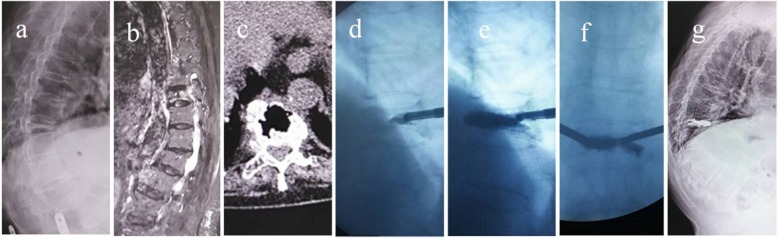

Fig. 2.

Preoperative, intraoperative and postoperative imaging findings of Kümmell’s disease. a Sagittal X-ray image showing the extreme compression and thinning of the diseased vertebrae. b Sagittal STIR image showing a band-like low intensity signal. c Coronal computed tomography image showing Th8 intravertebral fluid and air-densities. d The bone cement injection in the beginning showed that the bone cement penetrates forward. e Sagittal C-arm image showed the favorable penetration of bone cement. f Coronal C-arm image showed the favorable penetration of bone cement. g Sagittal X-ray image postoperatively showed the favorable penetration of bone cement